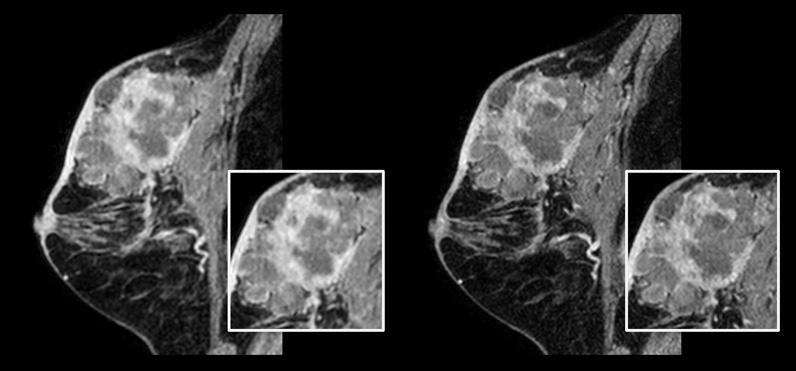

Links: Herkömmlicher 3D-mDIXON-XD-Scan mit isotroper Voxelgröße von 1,0 mm, Scandauer 2:22 Minuten Rechts: Compressed SENSE 3D-mDIXON-XD-Scan mit isotroper Voxelgröße von 0,8 mm, Scandauer 2:21 Minuten

Mit freundlicher Genehmigung von: Kurashiki Zentralkrankenhaus, Okayama. Japan

Bei Brustuntersuchungen ist eine hohe Auflösung wichtig, um sehr kleine Brustläsionen zu erkennen. Wir benötigen also T1- und T2-gewichtete 2D-Bilder in hoher räumlicher Auflösung, aber auch eine kurze Scandauer. Mit Compressed SENSE konnten wir die räumliche Auflösung und damit auch unsere Diagnosesicherheit erhöhen.“

Dr. Takashi Koyama, MD, PhD, diagnostischer Radiologe und Leiter des Radiologiezentrums und der diagnostischen Radiologie, Kurashiki Zentralkrankenhaus, Japan